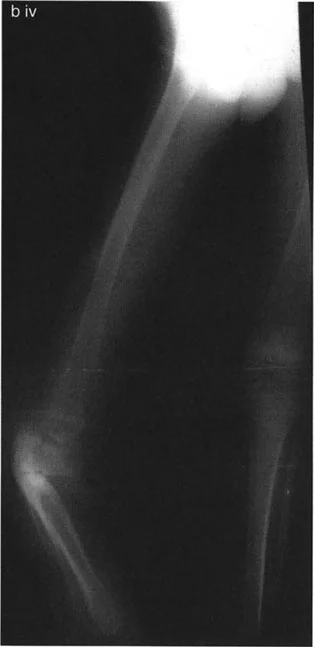

على عكس تشوهات الانحراف الزاوي التي تكون واضحة في الأشعة السينية التقليدية، فإن تشوهات الدوران خفية وتتطلب تقنيات تصوير خاصة وتحليلاً هندسياً دقيقاً.

تحليل دوران الفخذ (Femoral Version Calculation)

يتطلب قياس زاوية دوران الفخذ (Femoral Version) صوراً إشعاعية خاصة تُعرف باسم "تحليل المستوى المائل". يحدد هذا التحليل مدى التواء عظم الفخذ حول محوره.

تحديد مستوى التشوه بدقة

إن تحديد المستوى الدقيق للتشوه الدوراني هو أحد أهم الخطوات في التخطيط الجراحي. على الرغم من أن الدوران هو تشوه زاوي في المستوى المستعرض، إلا أن موقعه على طول العظم (قريب من المفصل أو بعيد عنه) يؤثر بشكل كبير على كيفية تصحيحه وتأثيره على الأنسجة المحيطة.

- في حالات ما بعد الإصابة: يكون مستوى التشوه واضحاً عادة عند موقع الكسر الملتئم.